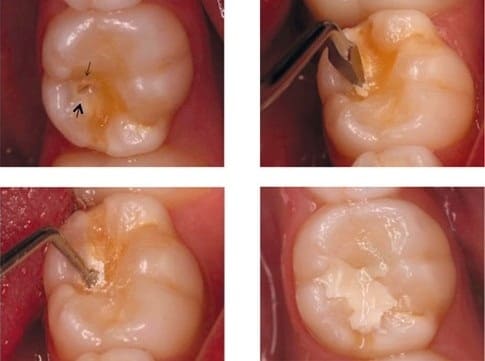

• Preventive procedures - Pit and Fissure Sealants, Topical Fluoride Application, Atraumatic Restorative Treatment